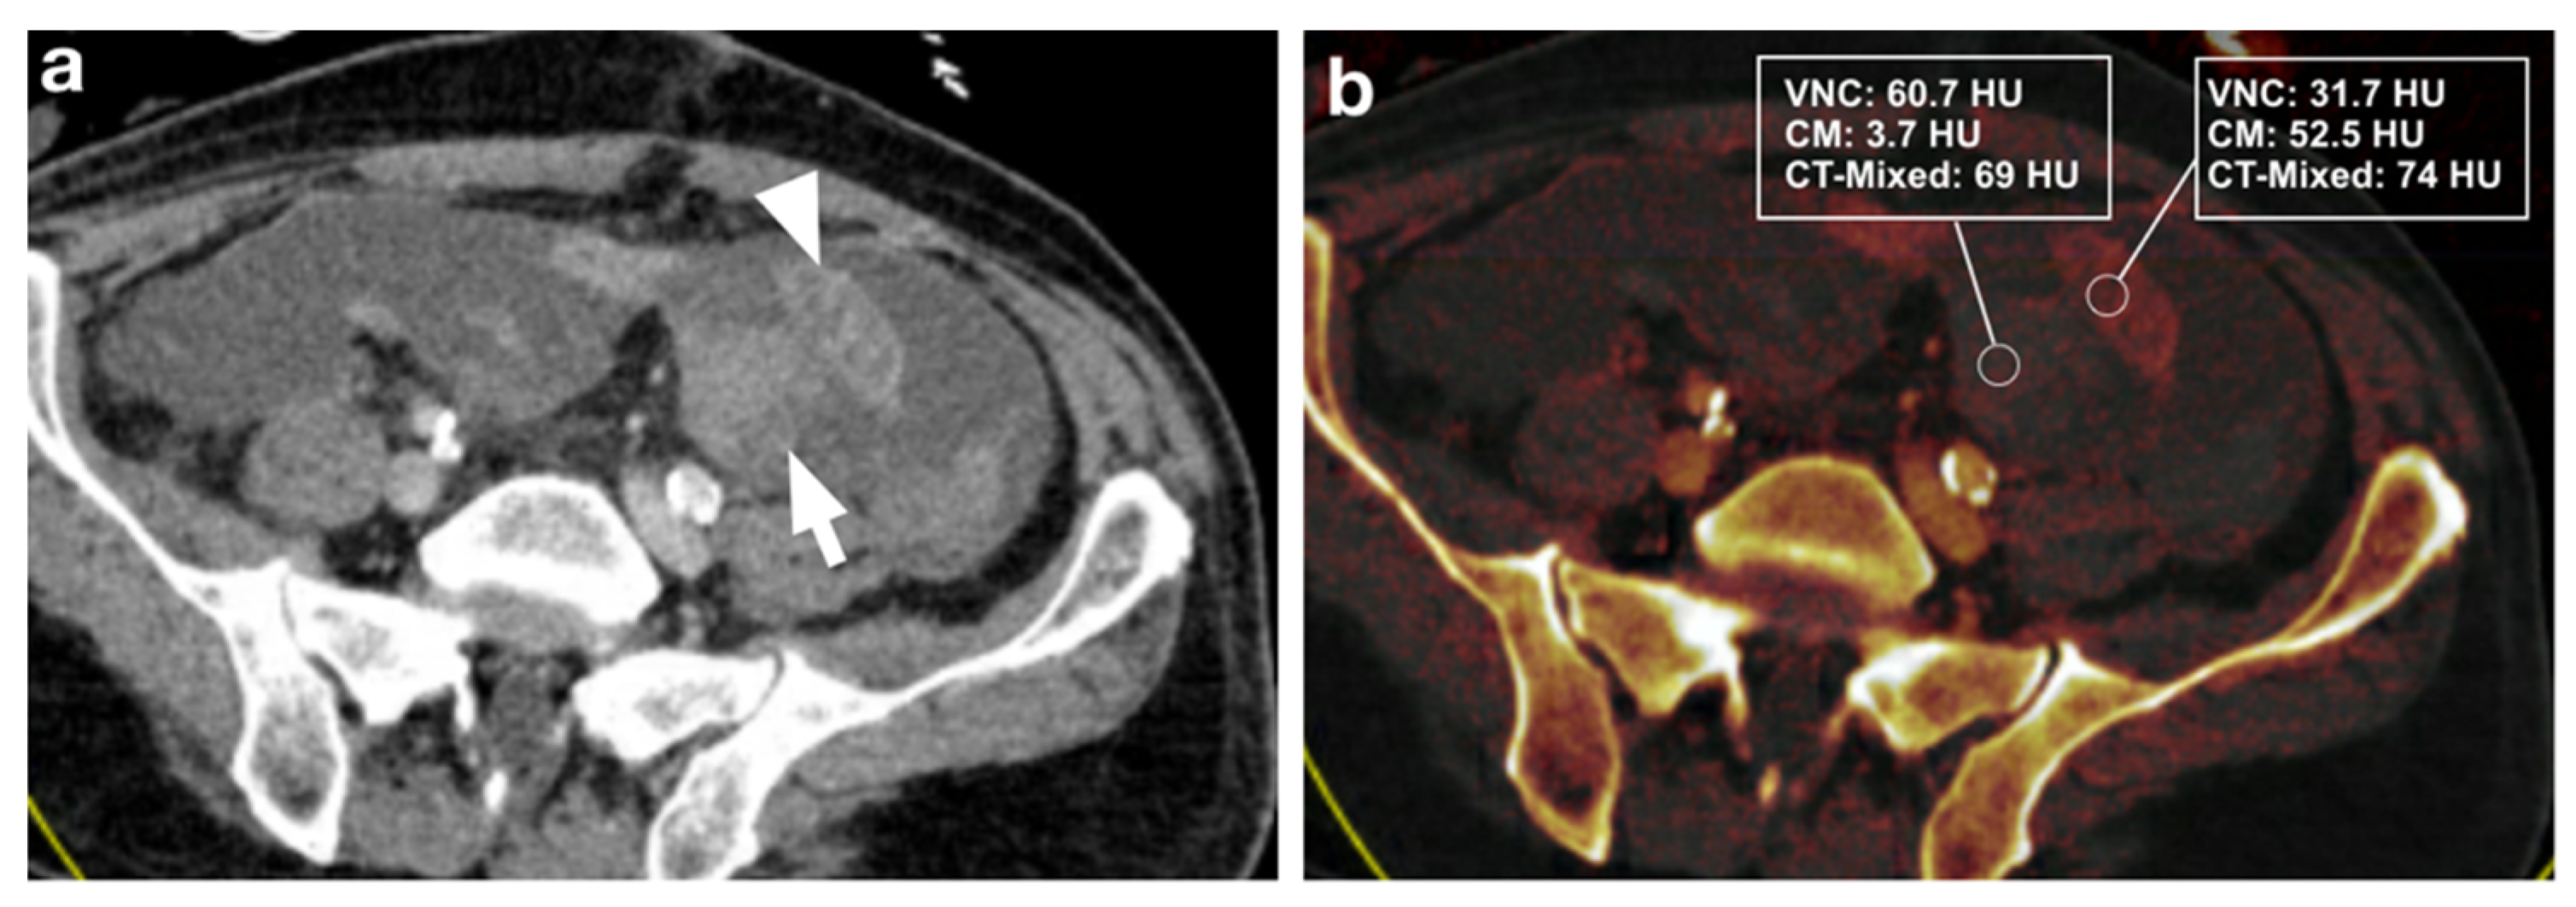

3.2.1. DECT Image Analysis